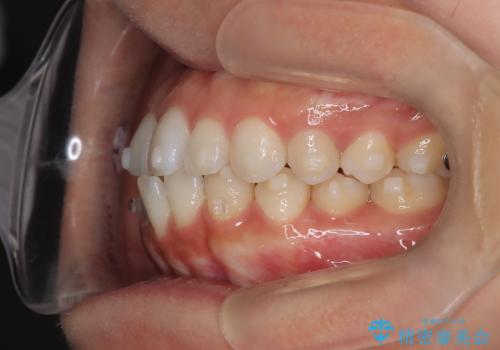

前歯の叢生を非抜歯で改善|インビザライン+IPR・遠心移動・FIX保定

- 前歯部のガタガタ(叢生)を非抜歯で改善するため、インビザラインによるマウスピース矯正を計画しました。抜歯は行わず、歯間をわずかに削るIPR(ディスキング)と奥歯を後方に移動させる遠心移動を併用して、歯を並べるスペースを確保します。歯列が整った後は、FIXリテーナー(固定式保定装置)で後戻りを防止し、安定した歯並びを維持します。

歯を抜きたくないというご希望に応え、インビザラインを用いて非抜歯で歯列を整えました。前歯に必要なスペースを確保するため、歯間をわずかに削るIPRと奥歯を後方に移動する遠心移動を組み合わせました。これにより自然で美しい歯並びを実現。治療終了後は、歯の裏側に目立たないFIXリテーナーを装着し、歯列の後戻りを効果的に防ぎました。患者様は治療中も審美的にストレスなく過ごされ、満足度の高い結果を得られました。